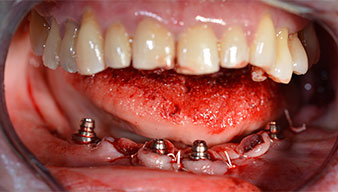

Tras la extracción de la dentición residual en el maxilar inferior, se realizó la incisión crestal en la región comprendida entre la pieza dental 37 y la 47.

A continuación, se identificó el agujero mentoniano (foramen mentale) como la estructura anatómica límite y se alisó el cortical de la cresta ósea con la pieza de mano recta y una fresa redonda grande (fig. 4).